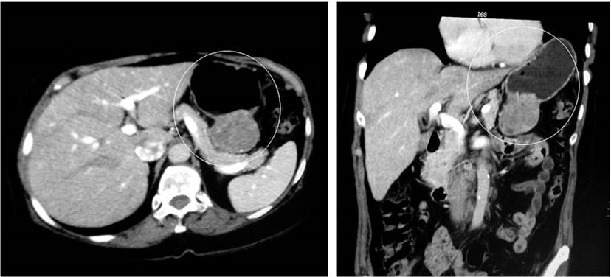

Se trata de una mujer de 68 años que consultó por un cuadro de 1 año de dolor en el epigastrio e hipocondrio derecho, asociado con la disminución de la ingesta de alimentos y, consecuentemente, pérdida de aproximadamente 6 kg en 8 meses. Tenía antecedentes de fibrilación auricular (FA) e hipertensión arterial (HTA), las cuales se encontraban en manejo con metoprolol y warfarina. En el examen físico había sensación de masa en el epigastrio, por lo que se indicó la realización de esofagogastroduodenoscopia, que reportó una lesión de 10 cm con centro deprimido y ulcerado y con presencia de fibrina. El reporte de patología no fue conclusivo. Adicionalmente, se solicitaron imágenes de extensión, en las que evidenció una gran masa en la curvatura menor del estómago (Figura 3). Con la sospecha de un tumor de GIST, fue llevada a gastrectomía subtotal no radical con reconstrucción en Y de Roux por laparoscopia.

A nivel intraoperatorio se demostró la presencia de un tumor exofítico en la curvatura menor de aproximadamente 7 cm, pediculado y no adherido a estructuras vecinas. La evolución posoperatoria fue adecuada, por lo que se egresó al cuarto día posoperatorio. El reporte de la patología evidenció un schwannoma con márgenes de sección negativos para compromiso tumoral (Figura 4). Con esta patología fue dada de alta por cirugía general.

Las imágenes diagnósticas suelen caracterizarse por ser lesiones bien circunscritas, con mínimos cambios en la fase arterial en la TAC y en la resonancia magnética (RM) usualmente son hiperintensas en T222.